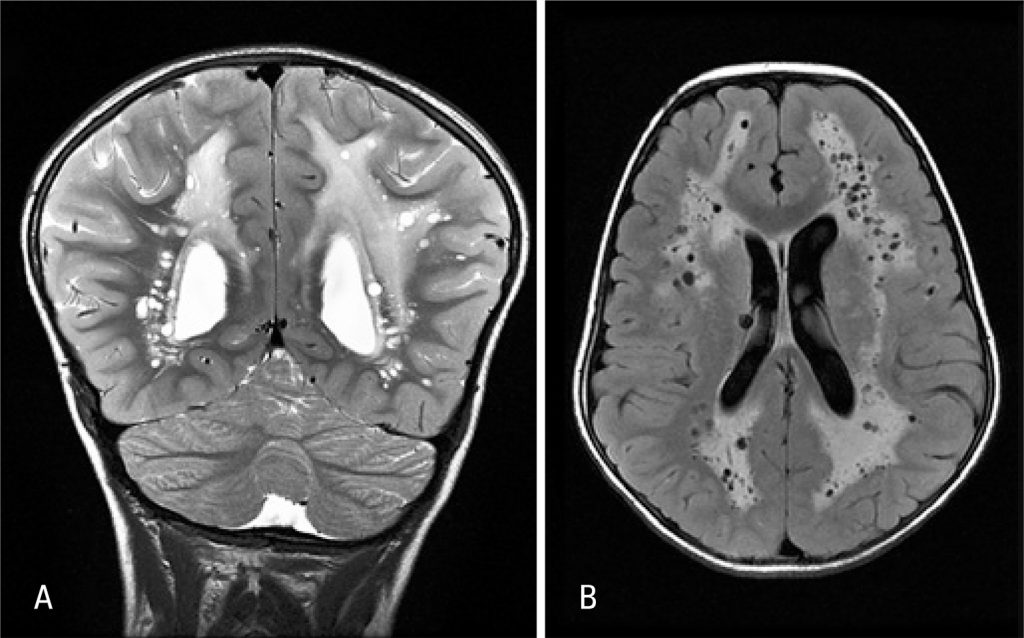

A previous healthy 7-year-old boy presenting occipital headache and constantly wake up at night with 1 week of evolution was admitted to our emergency service. He had linear hypopigmented macules along the lines of Blaschko affecting hemithorax and left upper limbs (). The patient also had macrocrania, antimongoloid palpebral fissure, changes in left eye pupil contour and syndactyly. A cranial computed tomography scan showed a hypodensity with accentuation of white matter and small cysts. Cranial resonance revealed an extensive process of leukoencephalopathy and multiple dilatations of perivascular spaces, being such findings rarely described in clinical feature of hypomelanosis of Ito (HI) ().